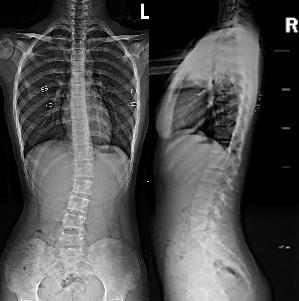

两张X光片,准确分型

如果家长连续3天自查发现异常,就要提高警惕,及时到医院进行复筛和专业评估。医生使用脊柱侧弯专用测量仪进行复筛,如果立位前屈时背部的倾斜读数超过5°则强烈提示存在脊柱侧弯。这种情况下医生会让孩子拍摄两张X光片,即站立位全脊柱正位片和侧位片。

X光片会直观地显示脊柱侧弯角度、弯弧位置、生长潜能及中线偏移等,这些数据会为后续治疗提供大量有价值的信息。

例如,侧弯角度决定了治疗方式的不同:

20°内的侧弯需要进行运动锻炼;

20°以上、45°以内的侧弯需要佩戴支具;

超过45°时手术成为治疗方式之一。

此外,医生会综合X光片表现来确定脊柱侧弯分型,例如,在主流的施罗斯运动治疗体系中包括了7个分型,它们是判断运动矫正方向及发力的重要依据。